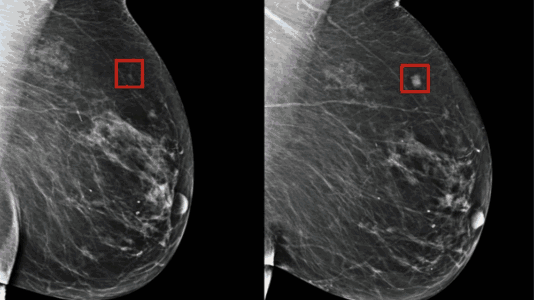

2.未来五年是否会患乳腺癌?MIT人工智能系统看X片就能预测

麻省理工学院计算科学和人工智能实验室与美国马萨诸塞州综合医院发布了一个全新的人工智能系统,该系统可以从乳房X光造影检查中预测患者是否会在未来五年内患上乳腺癌。据悉,这一模型学习了6万余名患者的乳房X线照片和已知结果,以了解乳腺组织中潜在恶性肿瘤的特征。